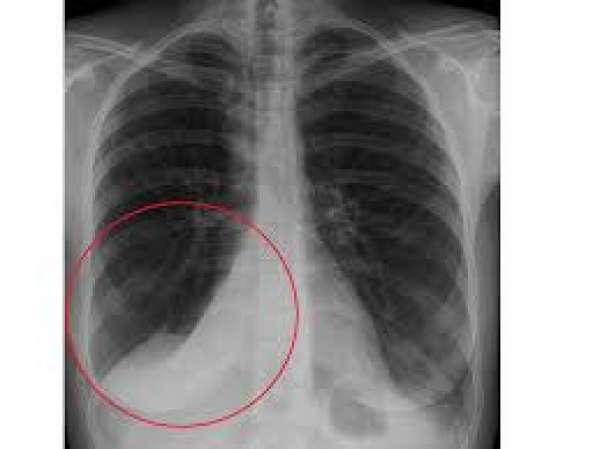

To measure the severity of atelectasis, researchers utilized scoring systems based on chest X-ray images. The findings revealed that Group B exhibited a significantly lower prevalence of complete or near-complete lobar atelectasis compared to Group A, with a notable emphasis on the results among male patients.

These results indicate that the Posthorax® vest plays a crucial role in reducing pulmonary complications post-cardiac surgery.